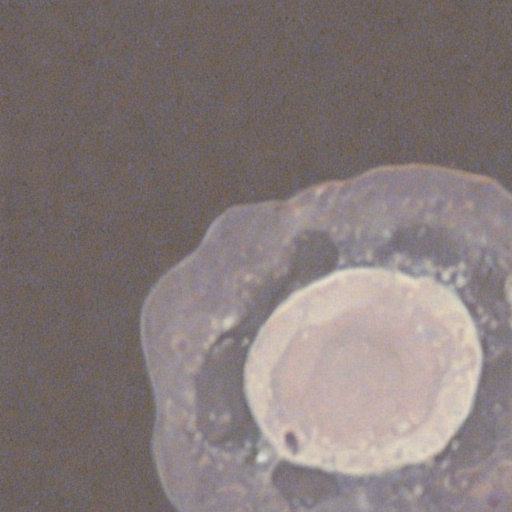

Despite recent advances, limitations still remain in cytomorphology, particularly regarding the generation of fine details for rare white blood cell classes with only few real samples. We here introduce a Cytomorphology Diffusion (CytoDiff) model for generating single white blood cells. It uses a few real samples allow to train a model capable of generating a large amount of synthetic data. Instead of applying traditional image augmentations, i.e., rotations, brightness, or color-jittering, CytoDiff is capable of generating new data that is not just a tuned copy of the originals, but novel instances that preserve biological plausibility, as illustrated in the comparison between real and synthetic single white blood cell images in Figure 1.

The image generation process has been successful for most cell classes; however, certain classes show less satisfactory results, as illustrated in the comparison between real and synthetic images in Figure 1. A notable example of this issue is the Promyelocyte Bilobed. The generated images presented in Figure S7, are characterized by a lack of sharpness, which complicates their recognition. This may be attributed to two primary factors. The primary and most apparent aspect is the quality of the real images. Despite the implementation of a manual selection process to identify the best real images to train CytoDiff, there are classes, such as Promyelocyte Bilobed, where the quality of these images is considerably lower in comparison to other classes. This phenomenon is explicable, as this particular cell type is uncommon. A promyelocyte with a bilobed nucleus is typically observed in patients diagnosed with acute myeloid leukemia.